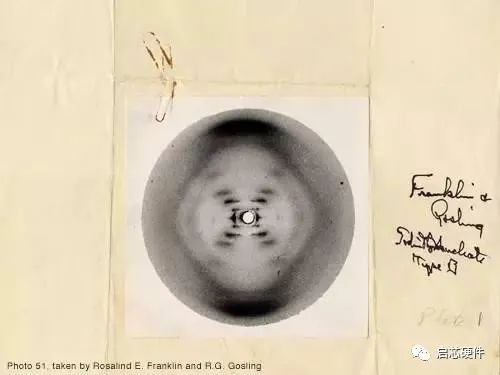

6. 照片51 - Rosalind Franklin (1952)

这照片真的叫做「照片51」,可想而知它的历史地位。其实这张X-光照片,证实了DNA的形态及结构,进而深远影响了遗传工程学及生物科技学,往后的故事大家都知道了。